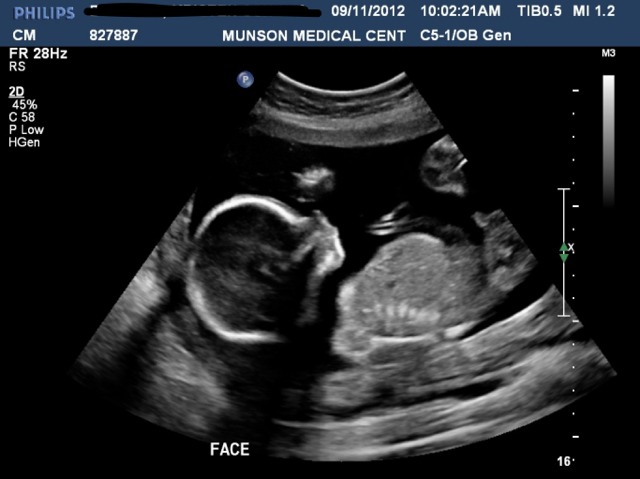

Here's the shot that has me wondering. What do you think?

Attachment 4519